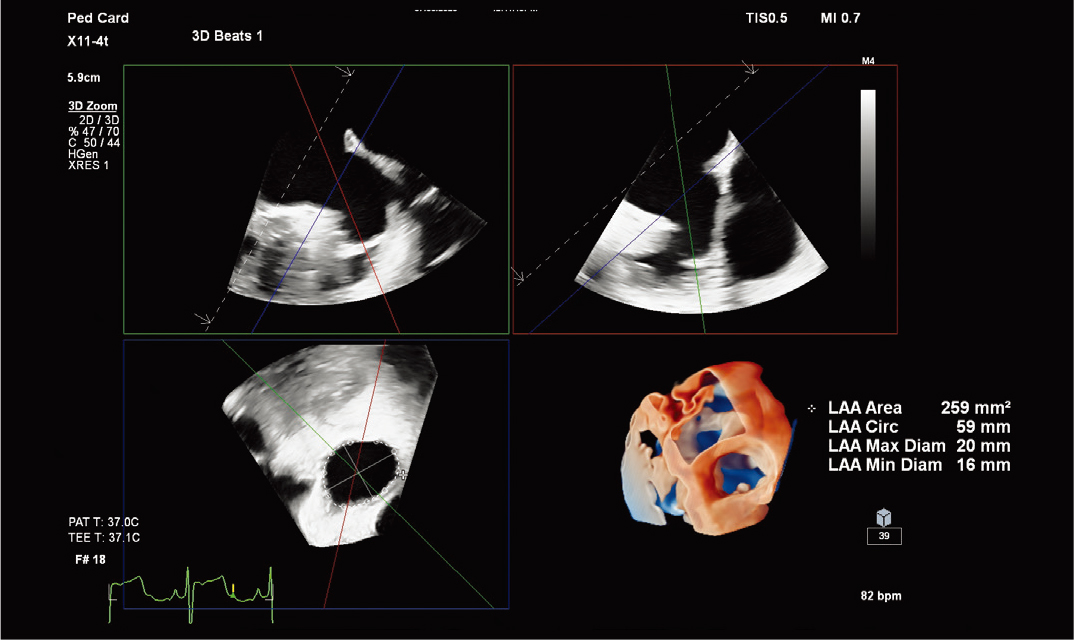

10适用于狭窄空间和复杂情况I使用全新 X11-4t 迷你 3D TEE 探头¹¹*,扩大 3D TEE 的应用范围。这款探头非常适合体型最小、体弱的患者,可扩大对儿科和成人患者的扫描范围。高效地执行手术,提高患者舒适度。X11-4t 探头与飞利浦创新产品组合集成,可与 VeriSight Pro 3D ICE** 在图像引导治疗中互补。

清晰、优质的 3D TEE 图像。

X11-4t 探头进行儿科左心耳评估 |